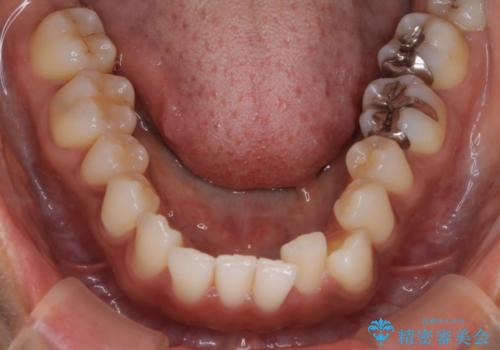

【インビザライン】前歯をきれいな歯並びにしたい

- 前歯の叢生を主訴に来院されました。このケースは抜歯をせずにIPRにてスペースを確保し、並べる計画をたてました。

きちんと使用時間を守って使用していただいたことで短い期間で治療が終了しました。